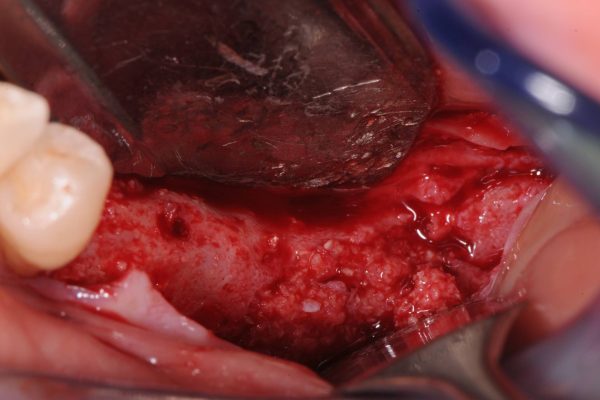

Importante perdita ossea Verticale ed orizzontale provocata dalla perdita di Impianti posizionati a causa della MANCANZA di una attenta diagnosi, piano di trattamento e capacità operativa, che avrebbero mostrato l’impossibilita di posizionare gli Impianti senza ripristinare lo spessore osseo adeguato …